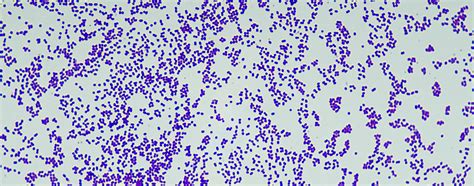

Gram-positive bacteria are classified by the color they turn after a chemical called Gram stain is applied to them. Gram-positive bacteria stain blue when this stain is applied to them. (Other bacteria stain red. They are called gram-negative.) Gram-positive and gram-negative bacteria stain differently because their cell walls are different.